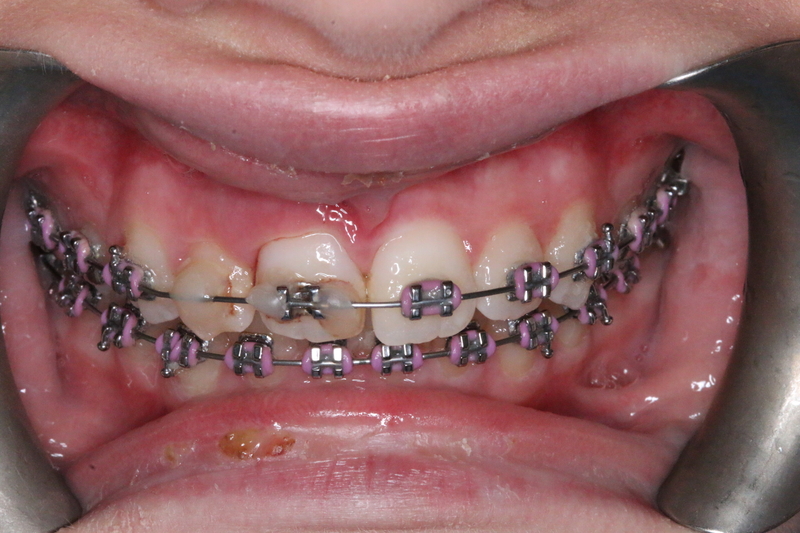

Case 5 – Dental Trauma

Severe Intrusion during braces